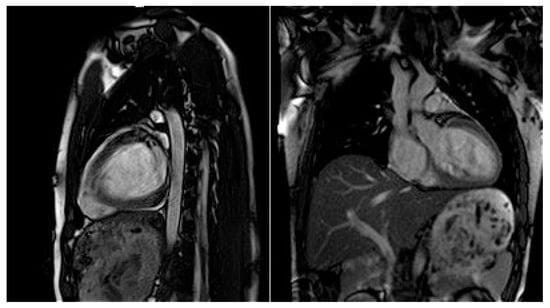

Moreover, dilated LV with decreased systolic function and global longitudinal myocardial strain were found in cardiac 2D TTE (transthoracic echocardiography) (Figure 2). Magnetic resonance imaging did not find myocardial fibrosis by LGE (late gadolinium enhancement), T1 and T2 mapping, and confirmed changes found on echocardiography (Figure 3).

Figure 3.

Cardiac magnetic resonance imaging with decreased LV systolic function and dilated LV.

Thus, the results of most studies suggest that DCM caused by pathogenic variants of the BAG3 gene detected at a young age is associated with rapid disease progression, life-threatening arrhythmias, poor prognosis, and survival. In our case, the patient was also young, 22 years of age at diagnosis, and an event recorder was implanted due to the risk of severe arrhythmias. Although our patient has been stable for three years, close monitoring is continued every year (dynamics of cardiac structure and function assessed by echocardiography and CMR at baseline and 1 year follow up are presented in Table 2) due to the high risk of sudden cardiac death.

Dynamics of cardiac structure and function assessed by 2D echocardiography and CMR at baseline and after 1 year.